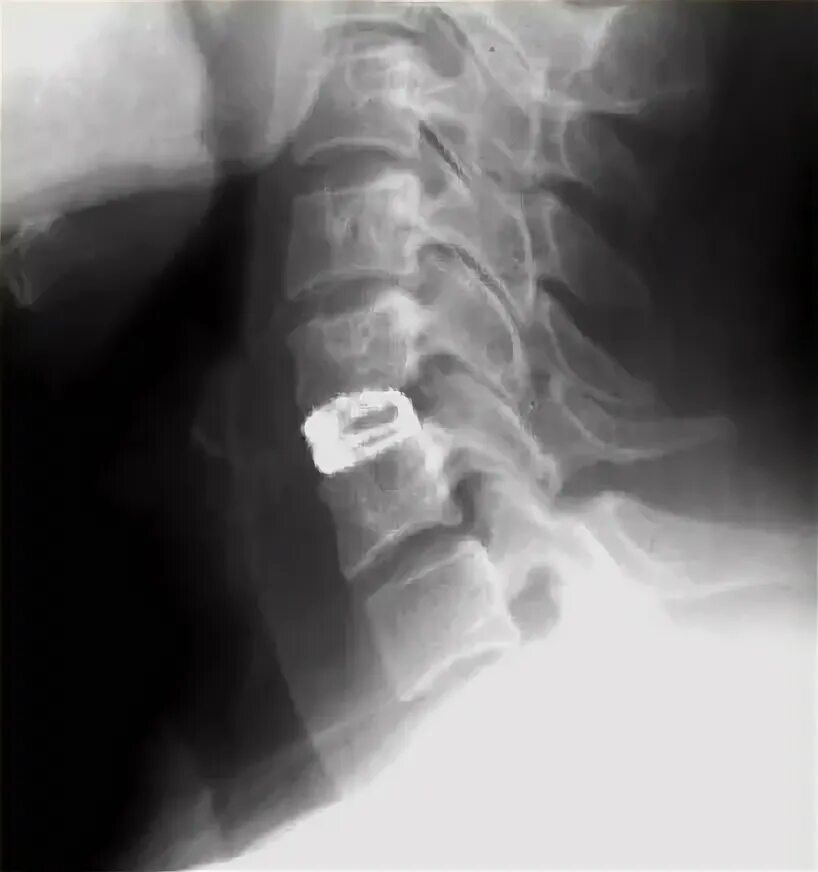

Установка кейджа в позвоночнике